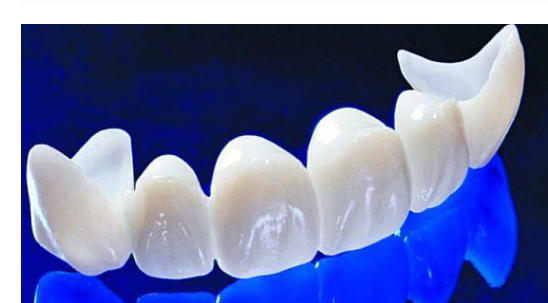

지르코니아 보철로 앞니를 교체하였습니다.

예전에는 pfm 보철을 많이 사용하였지만

오늘 환자분처럼 깨질 수 있고

시간이 지나면서 잇몸 부분이 까맣게 보일 수 있는 단점이 있어

요즘에는 강도도 튼튼하고

심미적인 지르코니아 보철을 대부분 사용하고 있습니다.